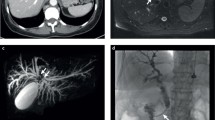

The MSK cohort (n = 186) and the TMA cohort (n = 309) were used to investigate the role of PNI in ICC (Fig. 1a, Table S3). PNI was evaluated by H&E staining and further confirmed by IHC of beta-tubulin III in TMA cohort (Fig. 1b) and was observed in 30.6% and 20.7% of patients in the MSK and TMA cohorts, respectively (Fig. 1c. f). The overall survival (OS) of patients with PNI was evidently shorter than that of patients without PNI (HR = 1.61, p = 0.013; HR = 2.33, p < 0.001, respectively) (Fig. 1d, g). Similarly, the relapse-free survival (RFS) of patients with PNI was conspicuously lower than that of those without PNI (HR = 1.95, log-rank p < 0.001; HR = 1.59, log-rank p = 0.017, respectively) (Fig. 1e, h). We also analyzed the relationship between PNI and other clinicopathological features and found that PNI positivity was significantly correlated with high CA19-9 level, the large duct type ICC and lymph node invasion in two independent cohorts. (Tables 1, S1). Recently, a multicenter study reported that PNI is a powerful and independent predictor of recurrence and survival in ICC [22]. Consistently, univariate and multivariate analyses of TMA cohort revealed that PNI (HR = 1.781, p = 0.002), microvascular invasion (HR = 2.033, p < 0.001), lymph node invasion (HR = 1.874, p = 0.038), and CA19-9 level (HR = 1.673, p = 0.003) are independent risk factors for OS in ICC patients (Fig. 1i). According to the 5th WHO classification, the large duct type ICC exhibited poorer prognosis than those with the small type, and PNI is usually observed in the large duct type ICC. To rule out the influence of duct type, multivariate analyses was performed and confirmed PNI was a negative risk factor (HR = 2.391, p < 0.001) independent of the duct type (Fig. S1a). Similarly, K-M analyses confirmed patients with PNI showed poorer prognosis either in the large duct type group (HR = 4.25, P < 0.001) or the small duct type group (HR = 1.72, p = 0.015) (Fig. S1b, c).

PNI is an unfavorable prognostic factor for patients with ICC post-operation. (a) Cohorts involved and study design of this article: ZS-ICC cohort (n = 255), cohort 4 and TMA cohort (n=309) are from Zhongshan hospital, Shanghai, China; MSK cohort is from a public database. (b) Representative images of H&E staining and beta-tubulin III staining of PNI in TMA cohort.(c) Fan chart of the components of MSK cohort: PNI positive cases accounted for 30.6% (n=57) of MSK cohort. (d) K–M analysis of OS between patients with and without PNI in MSK cohort (HR = 1.61, 1.06–2.44, P = 0.013). (e) K–M analysis of RFS between patients with and without PNI in MSK cohort (HR = 1.95, 1.33–2.86, P < 0.001). (f) Fan chart of the components of the TMA cohort: PNI positivity accounted for 20.7% (n = 64) of TMA cohort. (g) K–M analysis of OS between patients with and without PNI in TMA cohort (HR = 2.33, 1.51–3.59, P < 0.001).(h) K–M analysis of RFS between patients with and without PNI in TMA cohort (HR = 1.59, 1.02–2.49, P = 0.017). (i) Forest illustration of univariate and multivariate analyses of OS in TMA cohort (HBV: hepatitis B virus; ALT: alanine aminotransferase; AFP: alpha fetoprotein; CA19-9: carbohydrate antigen199; HR: hazard ratio; CI:confidence interval)